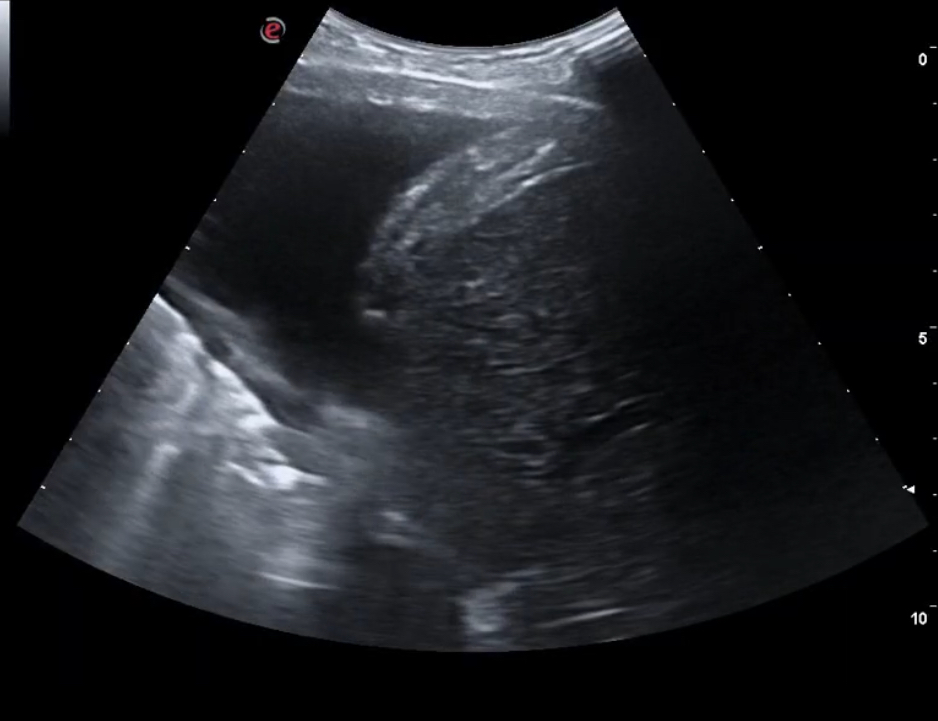

Se decidió realizar ecografía clínica pulmonar apreciándose líneas B en campos 2-4-6 de ambos pulmones con derrame en ambos senos costofrénicos visualizándose la cola de sirena y vena cava congestiva. La ecocardiografía realizada por los cardiólogos no mostró defectos en la contractilidad.